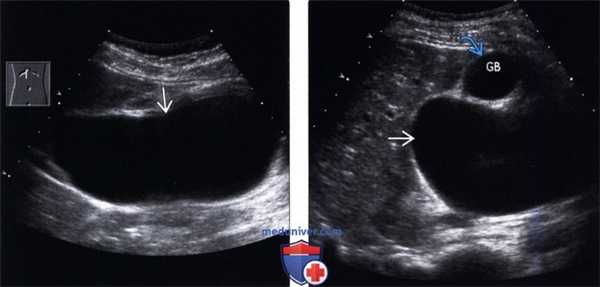

(Левый) На рисунке показаны множественные не вызывающие обструкции конкременты дистальной части общего желчного протока и желчного пузыря.

(Правый) На продольном УЗ срезе в просвете общего желчного протока определяется отбрасывающий тень эхогенный очаг, соответствующий конкременту. Общий желчный проток лежит спереди от печеночной артерии и воротной вены. Печеночная артерия идет между воротной веной и общим желчным протоком. (Левый) Дальше в каудальном направлении в просвете общего желчного протока в виде эхогенных отбрасывающих тень очагов определяются еще несколько конкрементов, тянущихся до уровня головки поджелудочной железы (цветовая допплерография помогает дифференцировать желчные пути от прилетающих сосудов).

(Правый) В дальнейшем при рентгеноскопии - эндоскопической ретроградной холангиопанкреатографии в просвете общего желчного протока определяется несколько дефектов заполнения, соответствующих конкрементам.